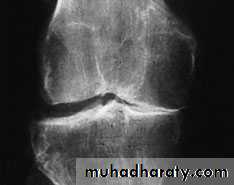

X-ray

The anteroposterior x-ray must be obtained with the patient standing and bearing weight; only in this way can small degrees of articular cartilage thinning be revealed.1-The tibio-femoral joint space is diminished

(often only in one compartment) and there is

2-subchondral sclerosis.

3-Osteophytes and

4- subchondral cysts

5-chondrocalcinosis are usually present and sometimes there is soft-tissue calcification in the suprapatellar region or in the joint

itself

X-ray weight bearing